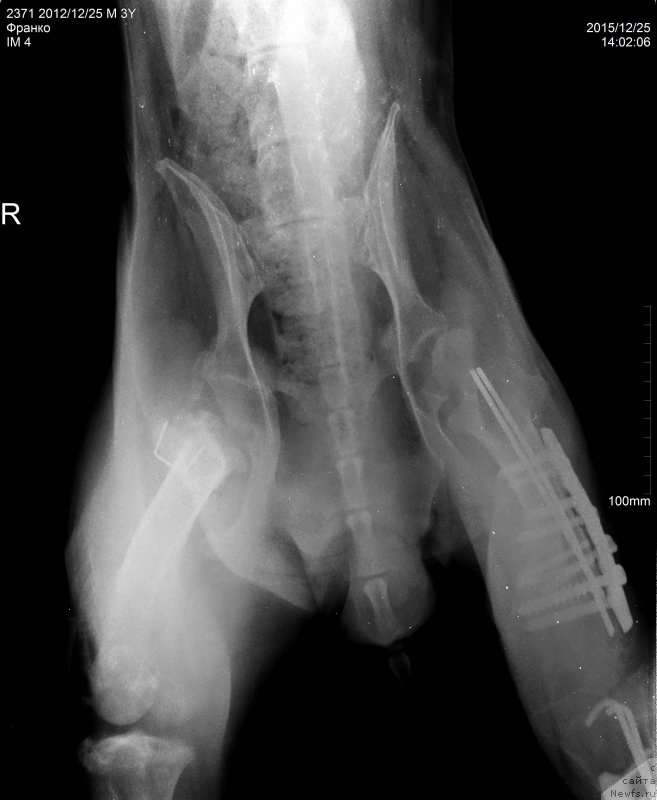

2015.12.25.=Франко снимки бедро латер

Фотография № 198290

2015.12.25.=Франко снимки голень

Фотография № 198291

2015.12.25.=Франко снимки таз ВД

Фотография № 198292

Артроз у Франко ужаснейший.

Хуже мне кажется уже и быть не может.

Ноги Франко так устроены, что он сам их разбивает.

Это чудо , что он еще на ногах,

Нужно чтоб пластины стояли как можно дольше.

Чудо, что Франко на ногах, радуйтесь каждому месяцу.

Это нам написала наша врач.